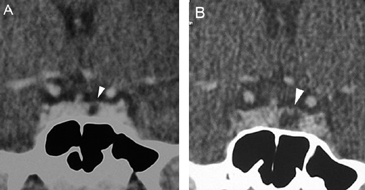

A diferencia de la tomografia computada, que emplea tubos de rayos X, la RM no utiliza radiaciones ionizantes, lo que es una ventaja a considerar en los pacientes pediátricos y en las mujeres embarazadas. La RM tiene una excelente resolución espacial y de tejidos blandos; por ejemplo permite precisar la presencia o ausencia de la neurohipófisis, lo que no es posible con la Tomografia Computada5-7. Con la TAC, con o sin medio de contraste yodado, es posible detectar microadenomas y macroadenomas pituitarios (Figuras 1A y 1B); sin embargo, en los macroadenomas puede ser difícil distinguir las relaciones del tumor con el quiasma óptico, o definir la invasión del seno cavernoso. Además, los artefactos producidos por amalgamas dentales deterioran las imágenes y la dificultad para lograr posiciones cómodas para los pacientes, con el fin de obtener cortes coronales directos, limitan la utilidad de la TAC.

En todo caso si la RM no está disponible o está contraindicada, por ejemplo en un paciente con un marcapaso cardíaco, la TAC con equipos de multicorte puede ser suficiente en la evaluación de microadenomas, teniendo presente que en estos tumores milimétricos la TAC tiene un 25% de falsos negativos; así, en estos casos los antecedentes clínicos y los exámenes de laboratorio son fundamentales8,9.

Figura 1A y B. TAC con contraste yodado, corte coronal, muestra un microadenoma lateralizado a izquierda (punta de flecha). Control a los 2 años. TAC con contraste yodado, corte coronal, demuestra aumento de volumen del microadenoma, lo que es infrecuente de observar en clínica (punta de flecha).